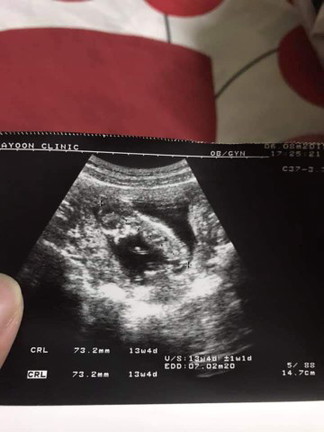

เมื่อวันที่6ส.ค.ที่ผ่านมา คุณหมอนัดไปอัลตราซาวด์เพราะอายุครรภ์จากการนับของคุณหมอครบ15weeks นั่นแปลว่าเราท้องได้3เดือนแล้วถูกต้องมั้ยคะ แต่พออัลตราซาวด์ดูขนาดตัวเด็กเสร็จเราดูในรูปที่คุณหมอให้มา ด้านล่างเขียน 13w 4dอันนี้คืออายุครรภ์จริงๆที่เราตั้งครรภ์มาเลยใช่มั้ยคะ